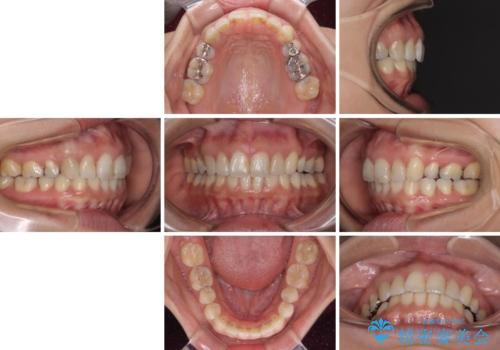

前歯の突出を軽減 インビザラインによる抜歯矯正

- 上の前歯の捻じれと突出感を気にして来院された患者様です。

目立たない装置を希望とのことで、上顎左右第一小臼歯を抜歯し、インビザラインにて矯正治療を行うこととしました。

インビザラインにて抜歯矯正を行うと、高頻度で奥歯が咬み合わなくなります。

抜歯スペースが閉じてからも咬みにくさ改善のためマウスピース矯正を継続するため、治療期間は長期化します。